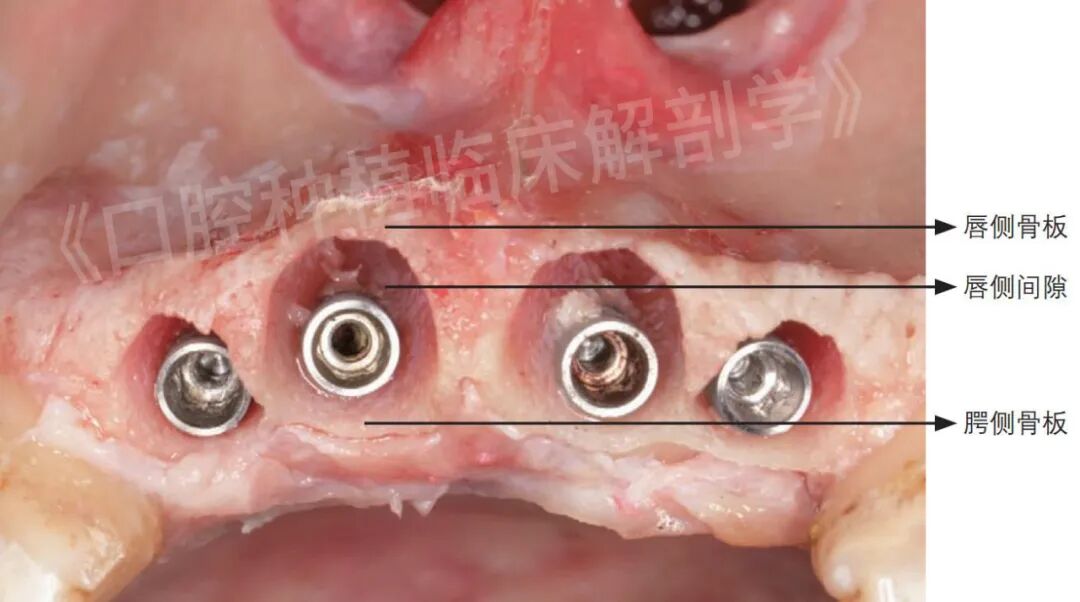

下颌前牙区即刻种植的标准骨性解剖术式要点 下颌前牙区由于其解剖结构的特殊性(唇侧骨板厚度菲薄、间隙小、唇侧倒凹),易造成邻牙牙根损伤及骨缺损,导致种植失败。下颌前牙区即刻种植种植体应稍微向舌侧放置,将种植体按牙体长轴放置在拔牙窝内,以确保唇侧骨壁厚度(至少2 mm),以维持长期稳定的效果,提高种植成功率。

图10~图16展示了冰鲜头颅下颌前牙区即刻种植案例,以供大家观摩参考。

图15 种植体唇侧骨板宽度。a为植入种植体后𬌗面观;b为种植体颈部与唇侧骨板的距离≥2 mm